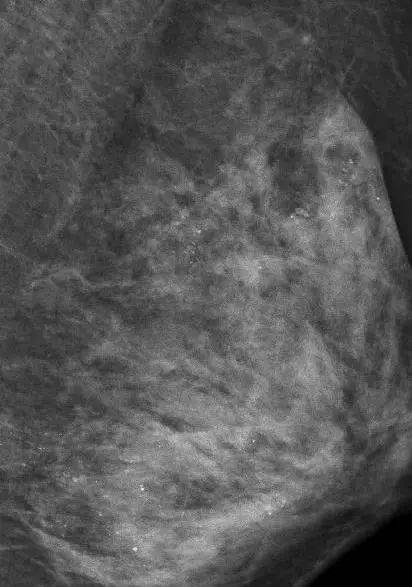

而朱女士未婚未育 半年前,她在体检时发现右侧乳腺内有一个2厘米大小的包块。最近,她感觉包块变大了,一周前到武汉市第一医院甲乳外科就诊,确诊为乳腺浸润性癌,做了全乳切除和淋巴结清扫手术。 乳房没了,但这场大抢救却依旧在进行。 医生在对她的左侧乳房进行乳腺X线检查时,发现里面全部都是细小如沙子一样的钙化灶,布满整个乳腺。 ▲在X光片下,朱女士的乳腺里满是星星点点的钙化灶 图片来源微博截图 究竟是什么原因造成的呢? 为寻找病因,医生详细询问了病史:“是不是做过什么治疗?” 朱女士否定了。 朱女士告诉医生,自己一向注重保养,这些年一直在外面做精油推拿按摩,保养胸部。 医生分析,极有可能是按摩师用力不当损伤了腺叶乳管,导致乳腺出现坏死性细小点状钙化。 其实这样的悲剧已经发生多起,随便一查,网上很多这样的新闻: 为什么这么说?看完下面这组图你就明白了。 可能有的人觉得,乳房是这个样子的。 ▽ 或者是这个样子的~ ▽ 但在乳腺科医生眼里,乳房的构造更像是这个样子... ▽ 对比一下 ▽ ■注意:女性在经期前后出现乳房胀痛是正常的,这是体内激素水平变化所致。 如果出现严重的胀痛不适,应当及时到正规医院找医生诊治,不建议盲目接受按摩治疗。万一有肿块,很可能在按摩刺激下短时间内迅速增大,甚至破溃扩散。 爱美之心人皆有之,现在不少养生馆、美容院,都有这样的按摩项目。 但一些不良商家为了赚钱,用一些看起来高大上的项目来欺骗你,不仅达不到美容的效果,甚至伤害身体。 卵巢保养 不少美容院都会宣传“卵巢保养”的种种好处:健康卵子、延缓衰老、调节痛经、良好睡眠、增强性趣……看到这么多功效,大家都会心动一下。 可实际上,“卵巢保养”不仅没有用,甚至还暗藏风险。 正常的卵巢,是按摩不到的! 很多美容院所说的卵巢按摩,其实就是抹点精油或药膏,按摩一下。实际上,因为卵巢位置在盆腔深处,一般按摩是根本触及不到卵巢的。 这些“美容按摩师”们真的只是在给你揉肚子。如果真的摸到了,那说明卵巢可能已经出问题,随意乱揉不仅不能保养,反而可能会按出事。 ▲卵巢位置示意图 乳房保健 很多美容院都宣称:乳房按摩可以治疗乳腺增生、乳腺纤维腺瘤等疾病,并且还有丰胸项目。 乳房乱按是会出事的。 乳腺增生主要和月经周期的激素水平变化有关,临床上95%的乳腺小叶增生不会癌变,绝经后也会慢慢好转,并不需要所谓的按摩保养。乱按反而会损伤乳腺! 排毒养生 “排毒养生”也是很多美容院的重头戏,从肾脏排毒、肝脏排毒再到大肠排毒,火疗、水疗、汗蒸……可谓是花样百出。 实际上人体不需要所谓的“排毒”。 首先,人体并没有什么毒 。出汗、排便……都是正常的新陈代谢过程,一些代谢废物会随之排出,但和排毒没什么关系。 其次,就算环境中有一些有毒有害的物质,我们还有皮肤、肝脏、免疫系统等器官来帮我们抵抗或清除它们。” ▲各种花式排毒不可信 淋巴排毒 淋巴如果出了问题,那么人体的免疫系统也会遭到威胁,所以淋巴排毒这种护肤疗程也是美容院常客。他们声称能排毒,刺激微循环,提升免疫力,舒压…… 这些功效都是想象出来的。 淋巴被病毒入侵的确会产生各种问题,但是想要把病毒排出也不是靠按摩淋巴就能获得的,护肤品更不可能从皮肤渗透到淋巴里杀死细菌病毒。 快速美白 有些女性对美白的痴迷程度可谓疯狂,可以不计一切代价去美白,而且又没有耐心,所以号称能快速美白的项目和产品就出现了。 这样的产品分外涂和内服,都有副作用。 外涂的产品大多含有铅汞,甚至激素,所以近年来皮肤科有越来越多激素依耐性皮炎患者,表现为面部皮疹、发炎、发红、发烫,对热越来越不耐受,出现红血丝等症状。当皮肤屏障受损,还会爆发黄褐斑。 而内服的其实就是美白丸,但实际上也有巨大安全隐患。美白丸一般都含有氨甲环酸、谷胱甘肽、半胱氨酸、vc等成分。但氨甲环酸、谷胱甘肽、半胱氨酸作为药物都是有副作用的,一定要谨慎使用。 本文首发:三甲传真(公众号ID:sanjiachuanzhen) 本文编辑:唐颖